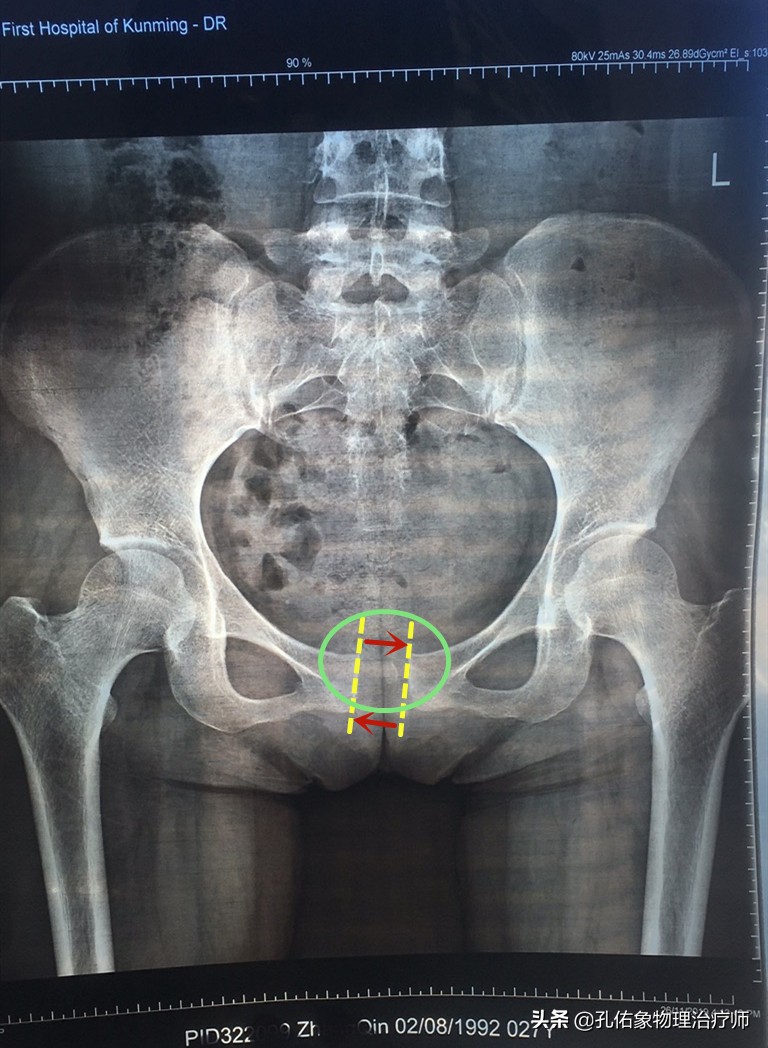

很多年轻女性,在怀孕期间,骨盆会随着激素和胎儿的变化而变化,或是在生产过程中,会阴区的撕裂伤等,都会导致耻骨联合的分离错位。如下图所示:

耻骨左右分离

耻骨上下移位

这样的错位,会在您不轻易的动作下产生大腿根部内侧缘的疼痛,一般会在产后一定时间内会自然愈合,不需要特殊的处理;若是一段时间没恢复的话,疼痛仍然存在,就需要前往医院,通过手法及骨盆运动等方式来修复。